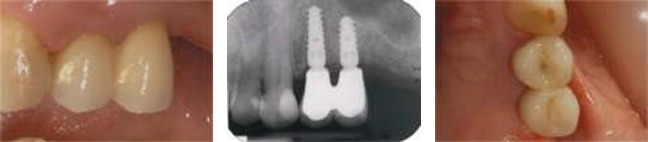

image028.png

(а)                                                      (б)                                                     (в)

image032.png

(г)                                                       (д)                                                    (е)

Рисунок 4: Через три месяца после установки имплантата делается окончательный внутриротовой слепок, изготавливается и доставляется пациенту окончательная реставрация с опорой на имплантат: (а) цифровой слепок с скан-боди из PEEK; (б) 3D-модель с циркониевым каркасом; © каркас из диоксида циркония устанавливается на постоянные титановые абатменты и проверяется на точность/точность (окклюзионный вид); (d) изготовление окончательной циркониевой керамики, зацементированной на окончательные титановые абатменты (вид сбоку); (e) периапикальная рентгенограмма при доставке окончательной реставрации с опорой на имплантаты; (f) 6-месячный контроль окончательной реставрации из циркониевой керамики (окклюзионная проекция).